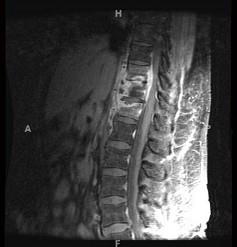

问题 女,67岁,突发右侧背痛半月余,请结合影像学检查,选择最可能的诊断 ( )

选项 A、脊椎结核 B、强直性脊柱炎 C、椎体压缩骨折 D、脊柱转移瘤 E、化脓性脊柱炎

答案 A